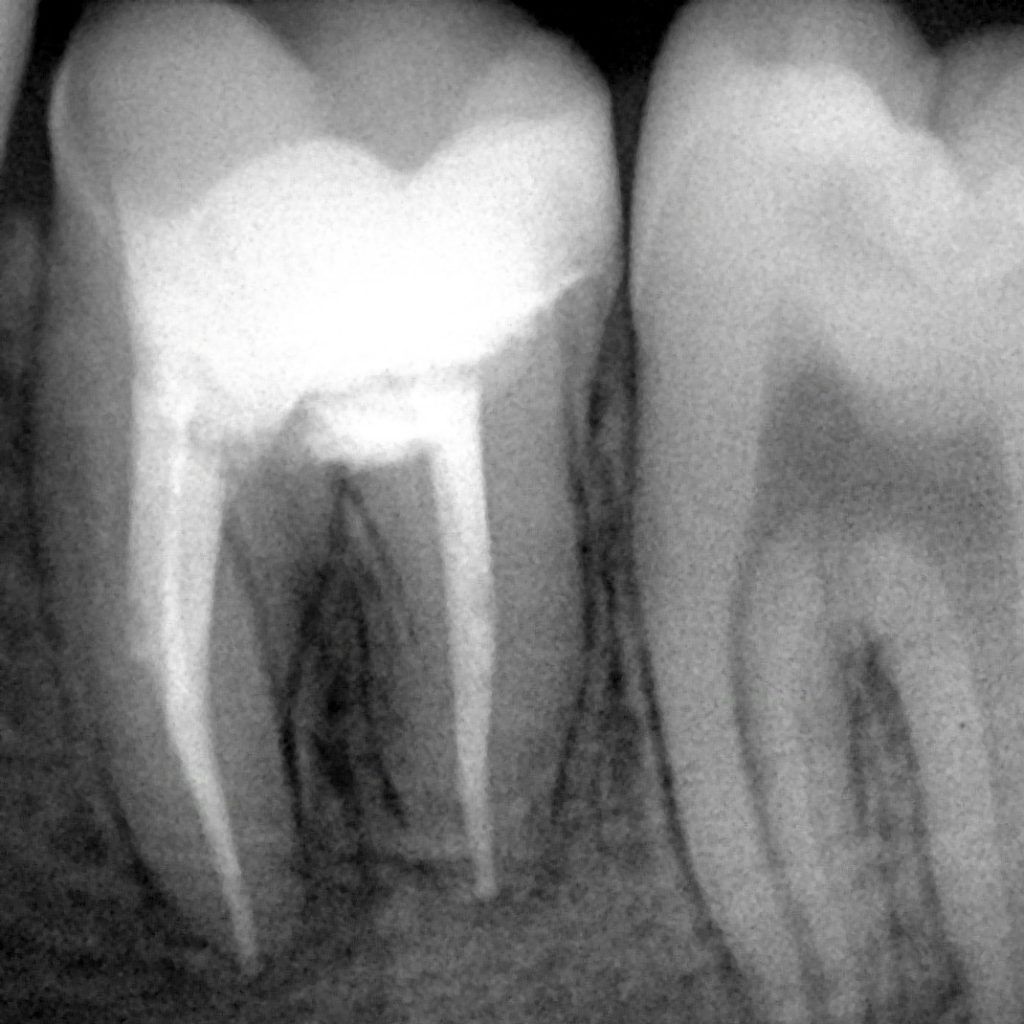

15 years old patient came to our clinic with pain in tooth no.46

After clinical diagnosis and x-ray we noticed structure of tooth is weak and hopeless and we noticed in x-ray the tooth is destructed and not restorable

Tp r.c.t and remove thin layer of cementom replaced by bio c putty to increase strength of tooth and finally we did a direct restoration because patient is under 18 in future need overlay or crown